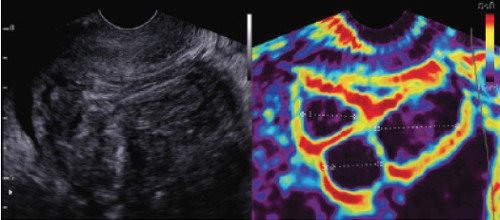

Эластографическое изображение, полученное с помощью технологии ElastoScan™.

Целью исследования было определить эластографические характеристики миометрия, ткани фибром и аденомиоза. Исследование проведено с помощью технологии ElastoScan (компании Samsung Medison, Республика Корея), позволяющей визуализировать различия в эластическом движении тканей.

Датчиком надавливают на матку, деформируя ее ткани. Степень деформации, вызываемой сжатием, зависит от жесткости ткани; более мягкие ткани деформируются сильнее, чем более жесткие. Выявленное изменение деформации, обозначаемое различными цветами, накладывают на соответствующее изображение в B-режиме.

На изображение в оттенках серого можно накладывать различные цветовые карты: черно-белую (a), сепию (b), с нарастанием цветов (c).

Использована карта с нарастанием цветов: темно-фиолетовый или темно-синий обозначает более жесткую ткань, зеленый и желтый - ткань средней жесткости, оранжевый и красный - мягкую ткань. На всех эластографических изображениях (динамических в стабильном состоянии) фиброма имеет правильную форму.